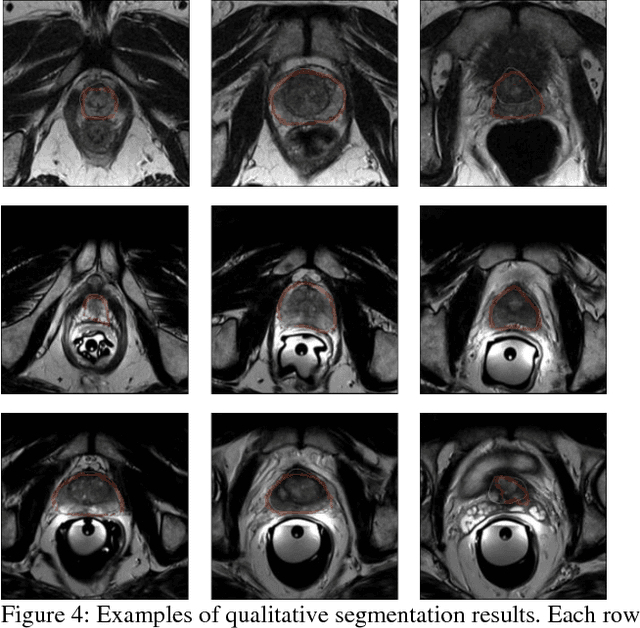

Abstract:The high incidence rate of prostate disease poses a requirement in early detection for diagnosis. As one of the main imaging methods used for prostate cancer detection, Magnetic Resonance Imaging (MRI) has wide range of appearance and imbalance problems, making automated prostate segmentation fundamental but challenging. Here we propose a novel Densely Dilated Spatial Pooling Convolutional Network (DDSP ConNet) in encoder-decoder structure. It employs dense structure to combine dilated convolution and global pooling, thus supplies coarse segmentation results from encoder and decoder subnet and preserves more contextual information. To obtain richer hierarchical feature maps, residual long connection is furtherly adopted to fuse contexture features. Meanwhile, we adopt DSC loss and Jaccard loss functions to train our DDSP ConNet. We surprisingly found and proved that, in contrast to re-weighted cross entropy, DSC loss and Jaccard loss have a lot of benign properties in theory, including symmetry, continuity and differentiability about the parameters of network. Extensive experiments on the MICCAI PROMISE12 challenge dataset have been done to corroborate the effectiveness of our DDSP ConNet with DSC loss and Jaccard loss. Totally, our method achieves a score of 85.78 in the test dataset, outperforming most of other competitors.